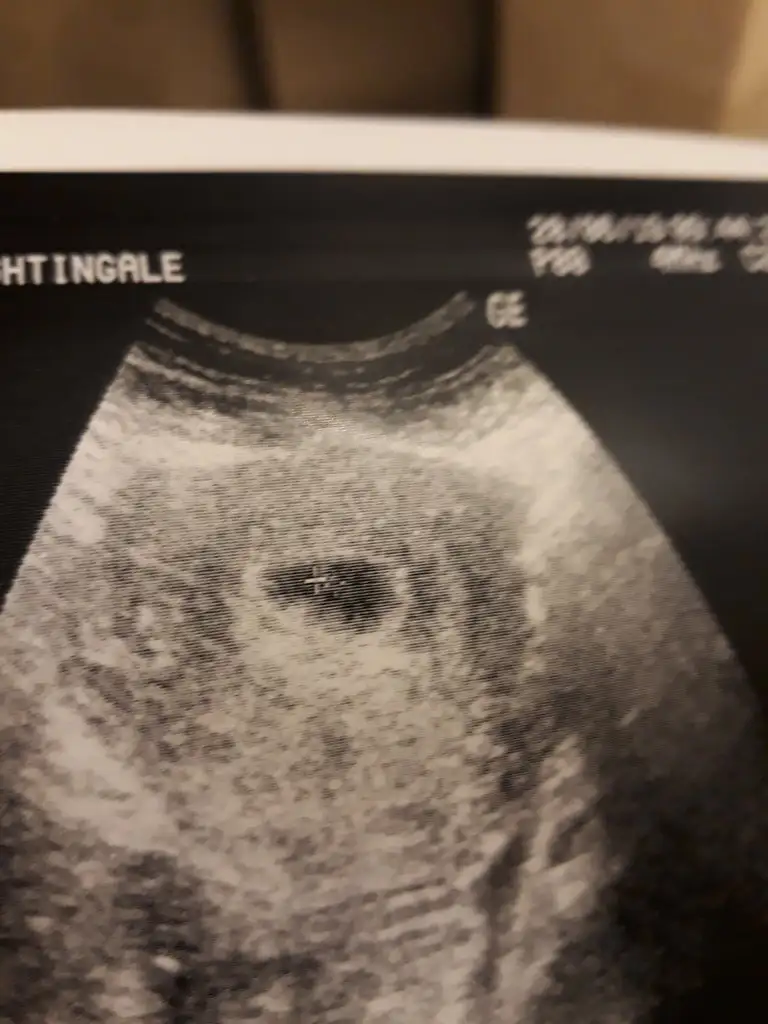

Günaydın kızlar bize 15 gün ilişki yok dedi dryolculuk olayını da sormadım. 15 gün sonra tekrar gel dedi guatr cıktı bende de normalde ramazan dan önce tüm tahlillerimi yaptırmıştım normaldi herşeyim hamilelil tetikledi sanırım ilaç kullanıyorum. Bende bebiş resmi atayım belki tahmin eden olur